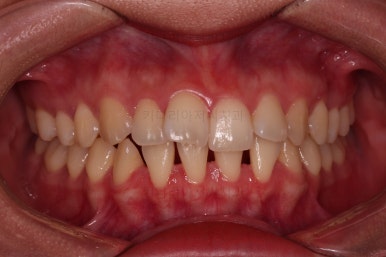

초진 시 입안의 모습입니다.

치열이 많이 삐뚠 것은 아니지만 앞니쪽이 삐뚤어 있고요. 아랫니 사이사이에 고루 틈새가 있네요.

윗니는 삐뚤고(공간부족), 아랫니는 틈새가 있다면(공간 과잉) 그 부조화는 부정교합을 의미합니다.

어금니 교합이 전반적으로 아랫니가 뒤로 빠져있는 교합이어서 맞물림이 좋지 못한 상태였어요.